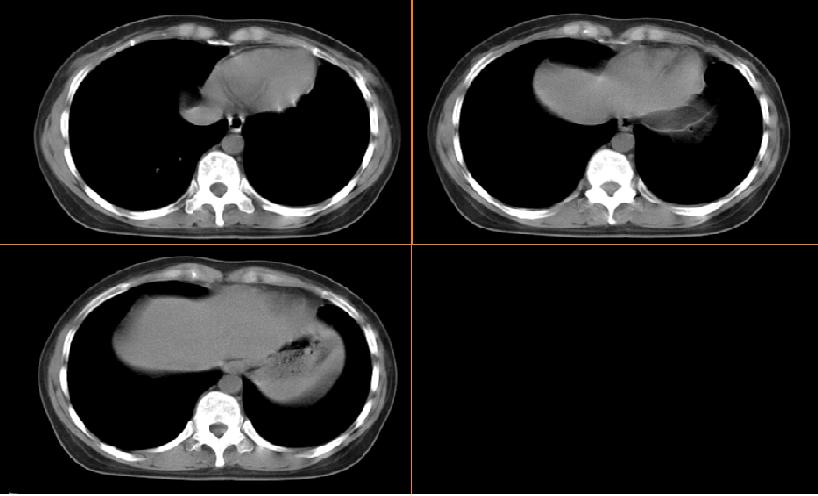

女,33岁,咳嗽5月。

左肺上叶前段致密,内见空气支气管征,相应部位胸膜增厚粘连,双肺上其他肺叶不同程度斑片状播散病灶,结合咳嗽5月的病史,考虑:双肺上叶继发性肺结核。

左肺上叶前段致密,内见空气支气管征,相应部位胸膜增厚粘连,双肺上其他肺叶不同程度斑片状播散病灶,结合咳嗽5月的病史,考虑:双肺上叶继发性肺结核伴左肺上叶肺含气不良。